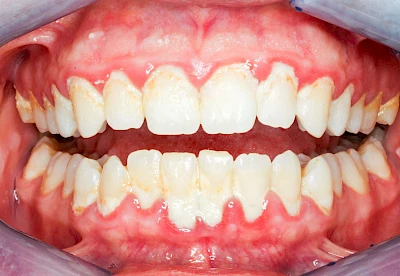

Bakterien in den Zahnbelägen greifen neben den Zähnen auch das Zahnfleisch (Gingiva) und den gesamten Zahnhalteapparat (Parodont) an. Der Körper reagiert mit einer Entzündung, sichtbar als Rötung und Schwellung. Meist blutet das Zahnfleisch z .B. beim Essen oder auch beim Putzen der Zähne.

Ist zunächst nur das Zahnfleisch von der Entzündung betroffen, spricht man von Gingivitis. Später, wenn auch der Knochen um die Zähne herum entzündet ist, spricht man von einer Parodontitis. Bei der Parodontitis wird der Knochen nach und nach abgebaut und das Zahnfleisch zieht sich zurück. Die Zahnhälse und Zahnwurzeloberflächen liegen mehr und mehr frei. Die Zähne werden zunehmend lockerer und fallen schließlich aus.

Bei Schwellung, Rötung oder Blutung des Zahnfleisches sollte neben der Intensivierung und Optimierung der Mundhyiene der Zahnarzt kontaktiert werden.